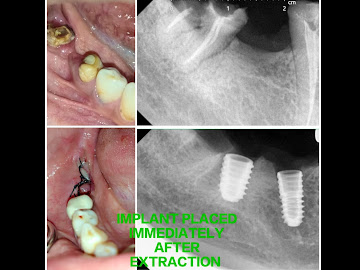

Gallery CASES DONE BY US DENTAL IMPLANT STAGE 2 SURGERYCOMPOSITE VENEERSDENTAL IMPLANT SURGERYCANINE EXPOSURE SURGERYWISDOM TOOTH SURGERYPOST AND CORE BUILD UP CALL US NOW